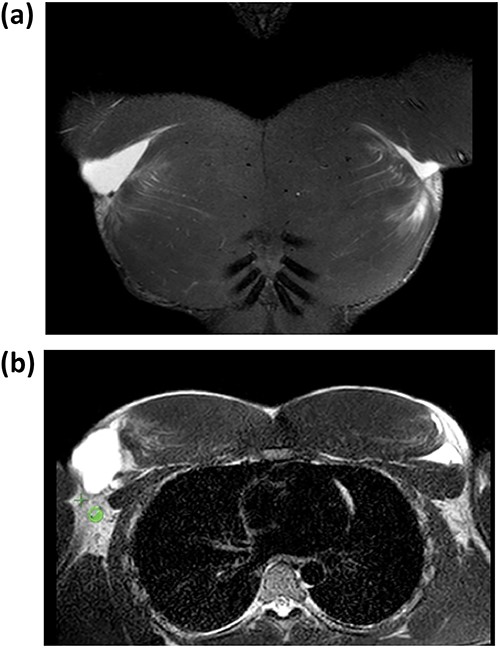

Coronal and axial T2-weighted MRI images showing rupture of the tendon of the bilateral PMM.